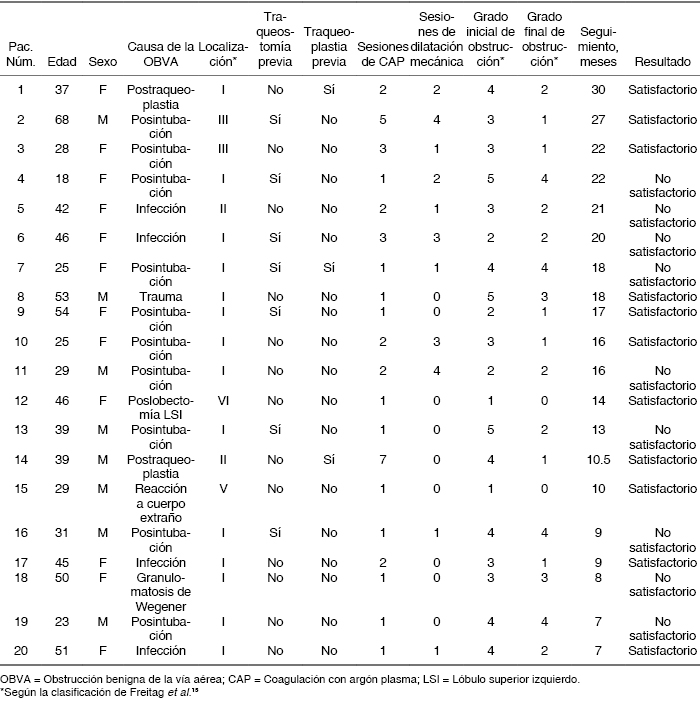

Definiciones: Con información obtenida del expediente broncoscópico, el grado y localización de la obstrucción fue clasificada según Freitag et al.(15) tal como se describe en la Tabla 1. Se consideró que existía mejoría satisfactoria después del tratamiento si había recuperación del lumen de la vía aérea con disminución de por lo menos un grado en la clasificación de Freitag asociada a mejoría de los síntomas.

Durante los dos años de estudio fueron diagnosticados 68 casos de OBVA de los cuales, 20 fueron tratados con CAP. La edad promedio de los pacientes fue de 38.9 + 12.8 años (rango 18 a 68), 12 (60%) fueron mujeres. La OBVA fue secundaria a intubación en 10 casos (50%); infección en 4 casos de estenosis traqueal (20%), 2 secundarias a tuberculosis y 2 a escleroma; traqueoplastia y laringotraqueoplastia en 2 casos (10%); lobectomía superior izquierda en un caso de obstrucción de bronquio principal izquierdo (5%); reacción inflamatoria por cuerpo extraño en un caso de aspiración de fragmento de proyectil al bronquio principal derecho (5%), granulomatosis de Wegener en uno (5%) y trauma penetrante de tráquea en un caso (5%). La localización de la obstrucción fue en subglotis en 70%, tercio superior de tráquea en 10%, tercio medio de tráquea en 10%, bronquio principal izquierdo en 5% y bronquio principal derecho en 5%. La Tabla 2 muestra las características clínicas de los pacientes incluidos y los resultados. Se utilizó CAP en todos los pacientes en un total de 38 sesiones (rango 1-7 sesiones por paciente) usando un broncoscopio flexible (Olympus(r) BF-1T180, Optical Co., Ltd., Tokyo, Japan) y equipo para CAP (Söring Arco 3000, Medizintechnik Germany), con sondas para argón de 1.8 mm (Argo-Flex-Prove, Medizintechik, Germany), una potencia programada de 25 W y flujo de argón de 0.2 a 0.3 L/min. Además, se realizó dilatación secuencial con dilatadores esofágicos de Jackson o cánulas orotraqueales de Rush de diferentes diámetros en 11 casos de estenosis laríngea o traqueal. En 23 de las 38 sesiones de CAP se usó anestesia general, en el resto anestesia tópica con lidocaína al 2% y sedación consiente con midazolam (5 mg, i.v.) y (fentanilo 150 μg, i.v.). Todos los pacientes recibieron dexametasona (8 mg, i.v.) cada 8 horas durante 3 días después de cada sesión de CAP.

En 11 casos (55%) hubo mejoría satisfactoria del grado de oclusión y de los síntomas, de los cuales 5 presentaron mejoría después de la primera aplicación de CAP que se mantuvo durante el seguimiento, y 6 tuvieron mejoría sostenida después de 2-7 sesiones de CAP. De los pacientes que presentaron mejoría satisfactoria 5 recibieron dilatación traqueal en una o varias ocasiones. En 6 de 7 casos que presentaron mejoría satisfactoria fueron resecados granulomas. En 9 pacientes no hubo mejoría por no haber presentado reducción significativa del grado de oclusión; entre estos, 8 presentaron mejoría mínima de los síntomas o del grado de oclusión y en un caso de estenosis completa subglótica no hubo cambios. Las Figuras 1 y 2 muestran ejemplos de casos con evolución satisfactoria y no satisfactoria respectivamente.

No hubo complicaciones relacionadas a la broncoscopia flexible o a la CAP. Hasta la conclusión del estudio, de los 9 casos con resultado no satisfactorio, 3 fueron sometidos a traqueoplastia, a uno se le colocó una prótesis de Montgomery en tráquea, 3 permanecen con traqueostomía y 2 cursan con vigilancia estrecha. El seguimiento promedio para todos los pacientes fue de 15.7 ± 6.4 meses (rango 7-30).